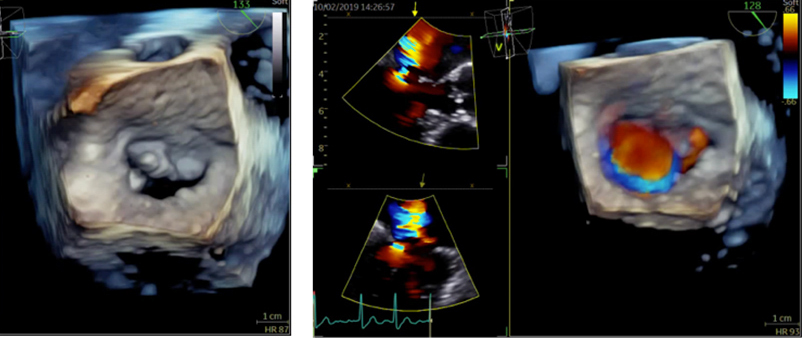

経食道心エコー検査

経食道心エコーは胃カメラとよく似た検査ですが、胃を見るわけではありません。胃カメラと同じような長い管を飲み込んでいただき、超音波を使って食道からすぐ隣の心臓の中を詳細に観察する検査です。心臓の中の構造やサイズが非常に細かくわかるので、この検査でなければ診断がつかない疾患もあります。3D技術がもっとも威力を発揮する検査です。

当院では静脈麻酔を用い、軽く眠っている間に検査を行いますので苦痛はほとんどありません。検査を行うのは医師で、看護師が付き添います。

所要時間は麻酔も合わせて30分〜40分程度です。